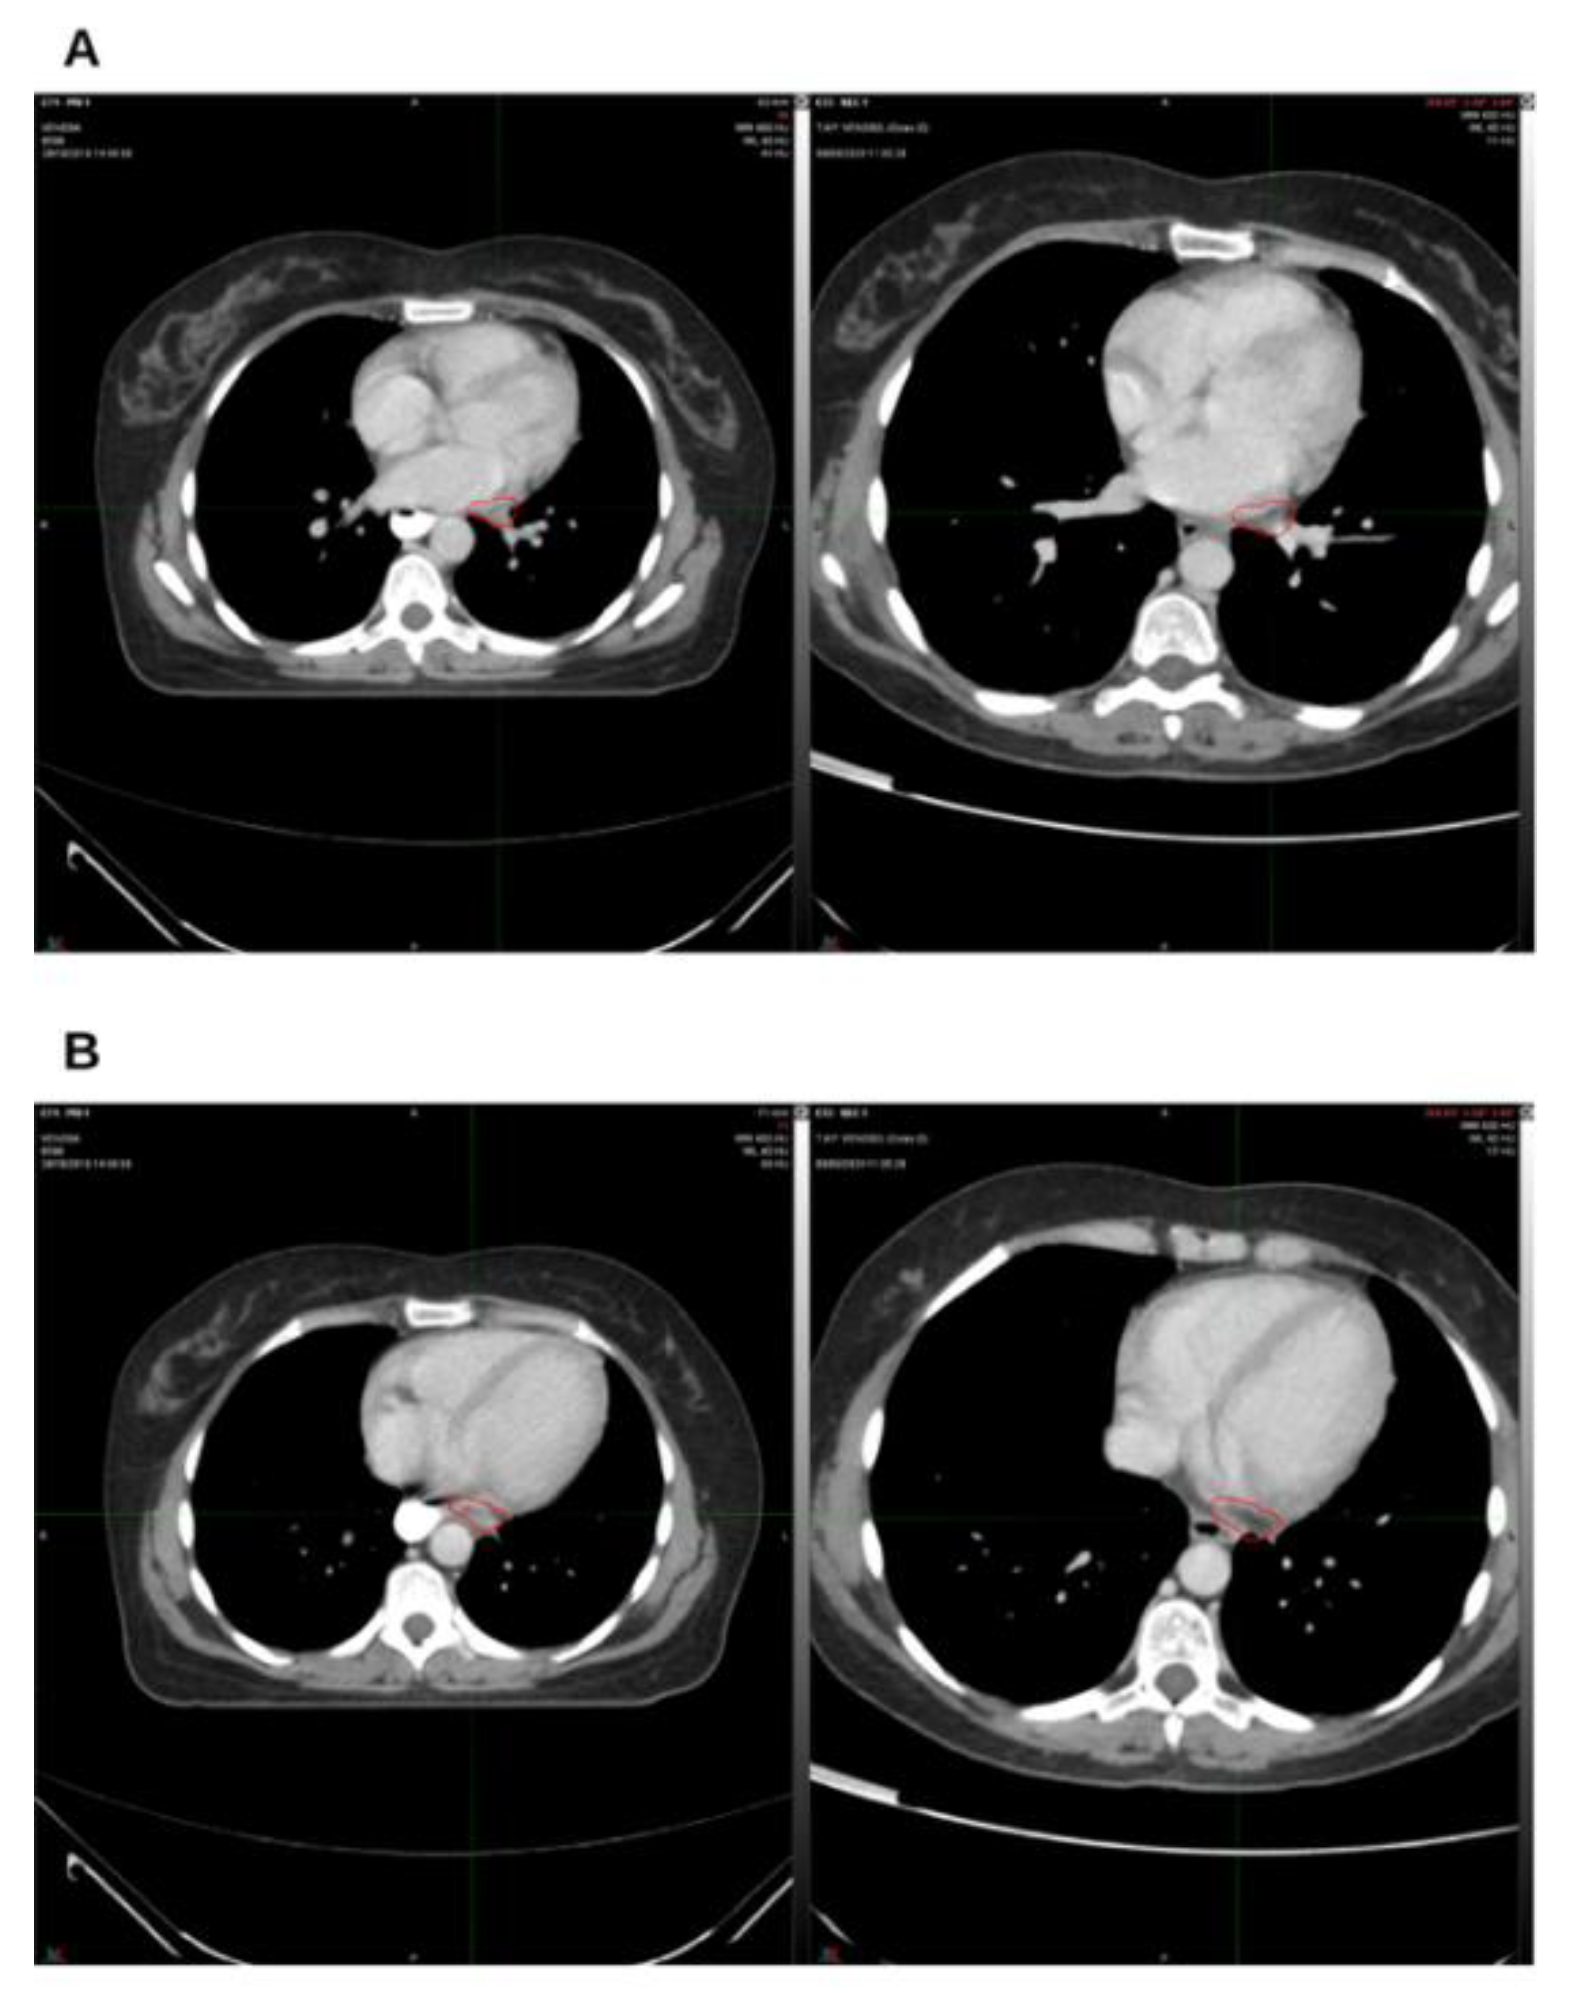

Background and Clinical Significance: Breast cancer is the most frequent malignancy in women. Advanced metastatic breast cancer is considered a treatable but incurable condition, with a median overall survival of only 2-3 years. Among its subtypes, triple-negative breast cancer (TNBC) accounts for a high proportion of breast cancer–related deaths. It is characterized by an aggressive clinical course, early recurrence, and a strong propensity for visceral and brain metastases. Case Presentation :We report the case of a Caucasian woman who, two years after being initially diagnosed and treated for TNBC, developed disease relapse with lung and mediastinal lymph node metastases. The patient received three months of chemotherapy combined with an adjuvant integrative protocol consisting of melatonin, cannabidiol, and oxygen–ozone therapy. This combined approach led to the complete disappearance of the lung nodules. Subsequently, stereotactic radiotherapy was performed and, in association with the ongoing integrative treatment, resulted in a significant reduction of mediastinal adenopathy. Introduction of immunotherapy, supported continuously by the same adjuvant strategy, achieved a complete and durable remission. Strikingly, the patient remained disease-free five years after the diagnosis of lung and mediastinal metastases. Conclusions: This clinical case highlights the potential benefit of using melatonin, cannabidiol, and oxygen–ozone therapy as part of an integrative approach in patients with aggressive metastatic TNBC. While it is not possible to establish causality from a single case, the sustained remission observed suggests that such unconventional adjuvant strategies could play a supportive role in enhancing the efficacy of standard oncologic therapies.